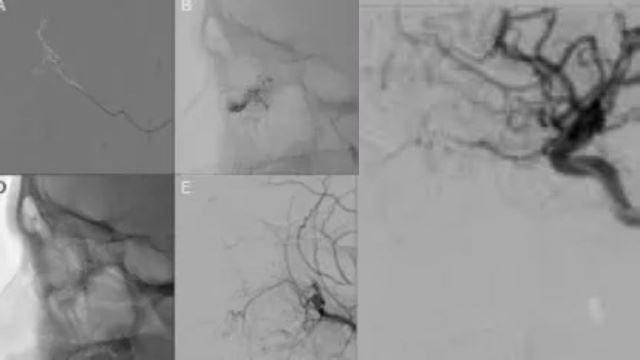

Selepas pemeriksaan lanjut, pesakit itu didapati mempunyai kecacatan pada saluran darah, selaras dengan kecacatan vaskular.

Selepas merujuknya kepada pakar neuroradiologi untuk ujian lanjut, budak lelaki itu didiagnosis dengan ‘kecacatan arteriovenous (AVM) mikro konjunktiva.

Dalam kes pesakit tersebut, AVM ditemui dalam konjunktiva forniceal inferiornya iaitu kelopak mata bawah.